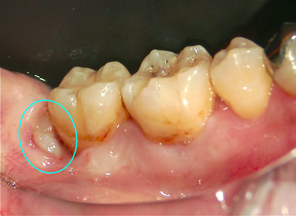

横向きに生える親知らず

コラム「横向きに生える親知らず」の画像